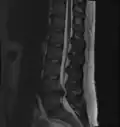

- Magnetic resonance imaging is the gold standard study for confirming a suspected LDH. With a diagnostic accuracy of 97%, it is the most sensitive study to visualize a herniated disc due to its significant ability in soft tissue visualization. MRI also has higher inter-observer reliability than other imaging modalities. It suggests disc herniation when it shows an increased T2-weighted signal at the posterior 10% of the disc. Degenerative disc diseases have shown a correlation with Modic type 1 changes. When evaluating for postoperative lumbar radiculopathies, the recommendation is that the MRI is performed with contrast unless otherwise contraindicated. MRI is more effective than CT in distinguishing inflammatory, malignant, or inflammatory etiologies of LDH. It is indicated relatively early in the course of evaluation (<8 weeks) when the patient presents with relative indications like significant pain, neurological motor deficits, and cauda equina syndrome. Diffusion tensor imaging is a type of MRI sequence used for detecting microstructural changes in the nerve root. It may be beneficial in understanding the changes that occur after herniated lumbar disc compresses a nerve root, and might help in differentiating the patients that need surgical intervention. In patients with a high suspicion of radiculopathy due to lumbar disc herniation, yet the MRI is equivocal or negative, nerve conduction studies are indicated.[44] T2-weighted images allow for clear visualization of protruded disc material in the spinal canal.

-

MRI scan of cervical disc herniation between C5 and C6 vertebrae -

MRI scan of cervical disc herniation between C6 and C7 vertebrae -

MRI scan of large herniation (on the right) of the disc between L4 and L5 vertebrae -

A rather severe herniation of the L4–L5 disc -

Example of a herniated disc at L5–S1 in the lumbar spine